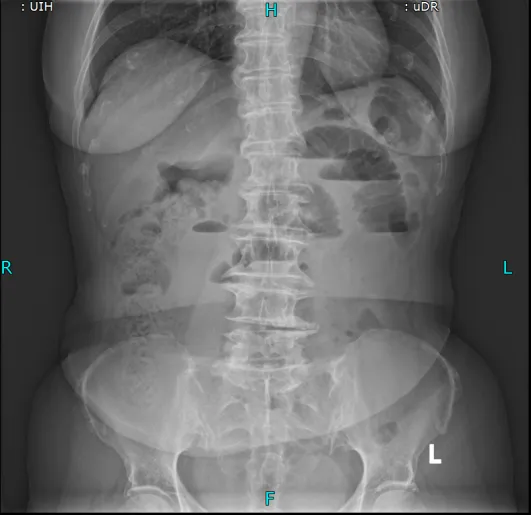

置入导管后肠梗阻明显减轻

考虑到王奶奶疼痛难忍、无法移动,普外科团队直接将胃镜设备推至病房床边,不到10分钟就完成了肠梗阻导管置入术。这根长达280cm的特殊导管不仅快速缓解了王奶奶的胀痛,还为后续治疗争取了关键时间,也为手术提供了安全保障。